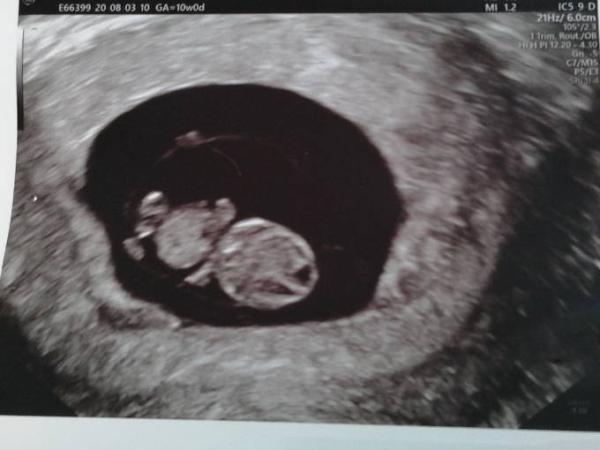

War gerade beim FA. Heute hat man endlich das Herz schlagen sehen habe dann auch meinen Mutterpass bekommen. ET ist am 1.4., ich sie meinte ich bin jetzt bei 9+0.

Bild zu Zurück vom FA - Forum für April - Mamis